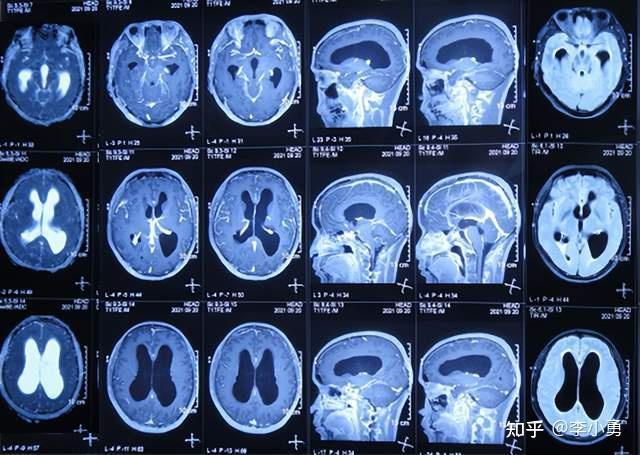

脑膜炎,即覆盖脑与脊髓表面保护膜发生的炎症,通常由感染引发。患者常表现出发热、头痛、颈部僵硬及意识障碍等症状。尽管脑膜炎大体上可预防,全球每年仍有百万例病例发生,导致数十万人丧生。为提升公众对脑膜炎的关注度,强调早期识别、诊治及预防,世界脑膜炎日设立于每年4月24日。

李斯特菌病的发病过程如下:李斯特菌为胞内寄生菌,能侵入细胞并在其中繁殖并传播。其潜伏期为3至70天。当人摄入受污染食物,细菌先在消化道定植,继而侵入肠黏膜上皮细胞,被巨噬细胞吞噬并输送至淋巴结系统、肝脏和脾脏。健康个体可通过免疫应答清除病菌,而免疫功能低下者,特别是细胞免疫缺陷者,则无法有效清除,细菌进而进入血液形成脓毒血症,通过血液抵达脑部等靶器官。一旦细菌穿越血脑屏障进入脑部,就会引发脑膜炎或脑干脑炎;感染孕妇则可能导致细菌经母婴垂直传播,引发胎儿或新生儿感染。

单核细胞增多性李斯特菌脑膜炎与其它细菌性脑膜炎相似,起病急,90%病例首发症状为发热,脑膜刺激征显著,伴剧烈头痛、眩晕、呕吐。通常伴有意识障碍,如木僵、谵妄,也可能发生抽搐。重症患者可在24至48小时内陷入昏迷。部分病例起病缓慢,病程较长且反复发作,若累及脑实质,可能出现脑炎和脑脓肿表现。个别病例发生脑干脑炎,表现出复视、发音和吞咽困难、面瘫和偏瘫等症状。警惕吃出来的脑膜炎。